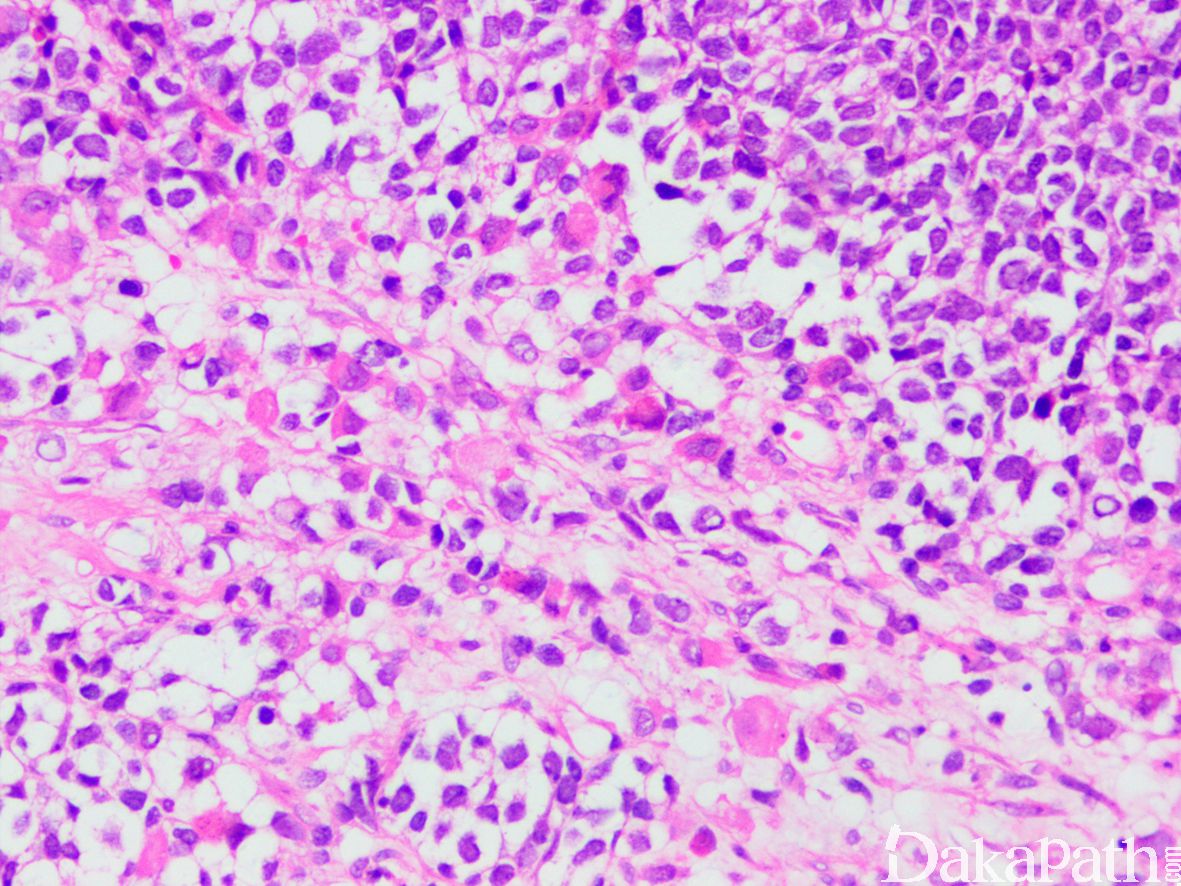

4. 瘤细胞排列成片状和巢状而贴附于纤维性间隔上,巢中央瘤细胞黏附性差,相互解离,形成特征性的假腺泡状或微囊状结构;

5. 肿瘤由未分化的原始间叶性细胞及少量早期分化的幼稚横纹肌母细胞组成;

6. 原始间叶性细胞呈圆形、卵圆形或小多边形,胞质少,核深染,核分裂像易见;

7. 腺泡中央的横纹肌母细胞多呈圆形或卵圆形,有时可见到胞质内横纹;

8. 部分病例可见散在的胞质淡染或弱嗜酸性,核位于胞质周边的多核巨细胞;